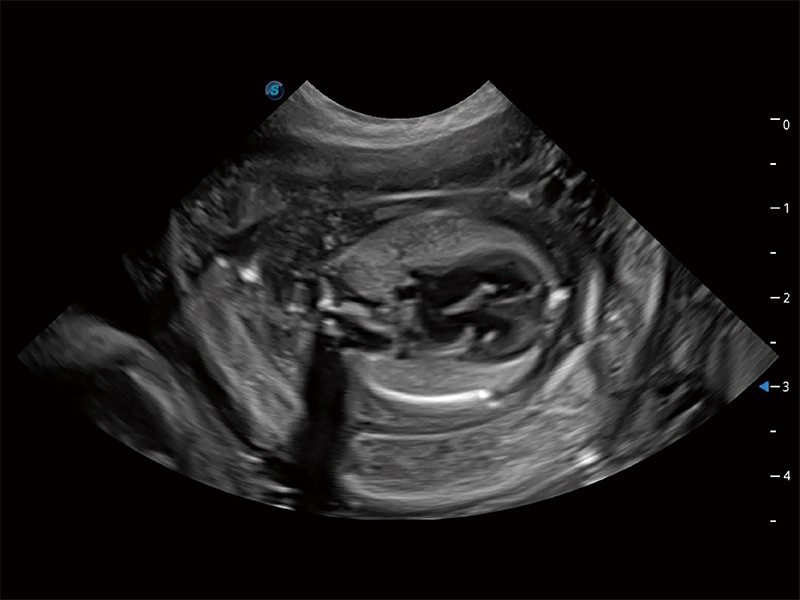

动物是人类最亲密的朋友和最值得信赖的伙伴。银河集团官网也一直致力于探索动物专用的超声影像解决方案。全新推出的ProPet系列,是银河集团官网在动物超声影像智能化、专业化、精准化的一次跨越式革新。动物不能用言语来表述自己的不适,通过超声影像,ProPet系列搭建了动物医生与不同物种沟通的“桥梁”,为动物医生注入了“治愈之力”。 ProPet 80 是银河集团官网匠心打造的一款高端动物专用彩超,采用性能卓越的全新硬件架构,极大提升超声系统的运行效率和数据处理能力,帮助动物医生从容应对日益增多的挑战性病例和日益多样化的临床需求。

高性能和先进的临床应用工具可以为动物医生提供临床信心。ProPet 80 搭载了先进的腹部和浅表应用工具,帮助医生在日常临床实践中发挥前所未有的作用。

ProPet 80 专为动物医生设计,对不同的动物体型和生理结构作出了针对性的优化。通过动物影像专用软件,可满足个性化的应用需求,帮助动物医生获得更精确的诊断数据。

为精细结构及组织边缘提供高清晰度的图像和更大的成像视野。帮助减轻医生的用眼疲劳,快速精准获得测量的数据。